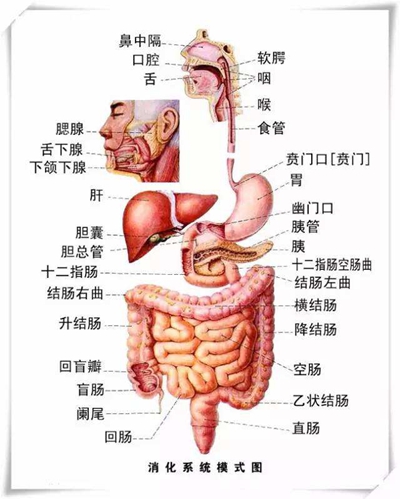

盲腸的位置 (50)

盲腸的位置 (6)

盲腸的位置 (7)

盲腸的位置 (8)

盲腸的位置 (9)

盲腸的位置 (46)

盲腸的位置 (47)

盲腸的位置 (48)

盲腸的位置 (49)

盲腸的位置 (5)

盲腸的位置 (42)

盲腸的位置 (43)

盲腸的位置 (44)

盲腸的位置 (45)

盲腸的位置 (41)

盲腸的位置 (40)

盲腸的位置 (30)

盲腸的位置 (31)

盲腸的位置 (32)

盲腸的位置 (33)